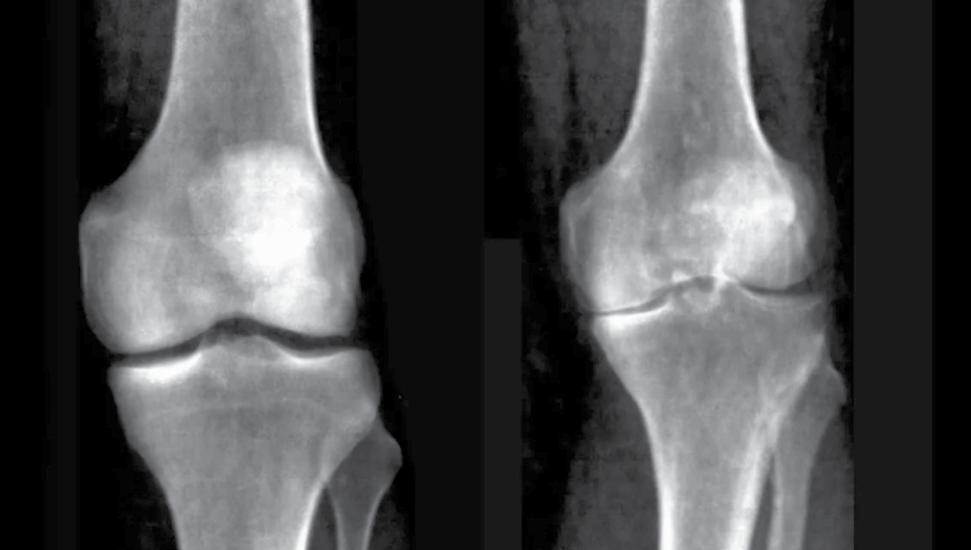

AI Tech Accurately Diagnoses Knee Arthritis from Medical Images

AlthoughMany people over the age of 50 develop arthritis of the knee, a painful condition that can make it difficult to do everyday activities like stand, walk or climb stairs. New research published in Nature Digital Medicine on the use of artificial intelligence to analyze medical images demonstrates the potential for improving diagnoses of knee osteoarthritis and predicting a person’s risk of developing it in the future.

A team led by researchers from The University of Texas at Austin’s College of Natural Sciences and Dell Medical School developed an AI model that can diagnose knee osteoarthritis with clinical-grade performance, based solely on images of the knee joint from medical x-rays. One potential application would be incorporating the model into existing software that technicians use to evaluate x-rays, flagging possible cases of knee

osteoarthritis to assist clinicians in making a diagnosis. The goal wouldn’t be to replace human doctors but to assist them.

Because arthritis of the knee is caused by the grinding of knee bones (the femur and tibia) against each other as protective cartilage wears down, the size of the gap between the bones is associated with how severe the condition is. This gap, known as the joint space can be used as a clinical biomarker to quantitatively assess disease severity. In their work the researchers were also able to provide automatic measurements on the knee joint space with high precision and

X-ray images of a healthy knee (left) compared to an individual with knee osteoarthritis. Credit: UK Biobank/ University of Texas at Austin.